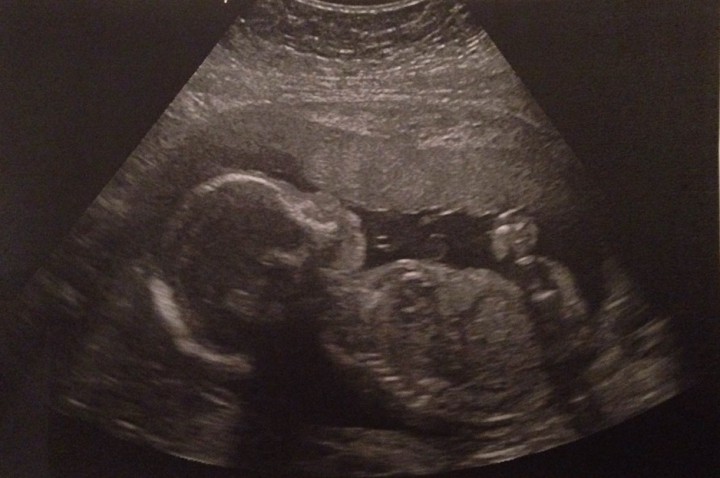

Baby Iver. Credit: Online campaign. Baby Iver / Online campaign